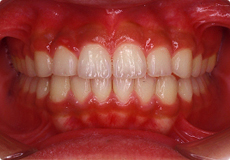

よい歯並びの例

矯正治療では、このような咬み合わせを獲得することが目標の一つとなります。

お口の中には、親知らずを除くと上下で28本の歯がはえます。

隙間や凸凹などもなく、アーチ状にきれいに並んでいます。

上下の真ん中が一致しています。

よい咬み合わせでは、前歯は上の歯が下の歯より2mmくらい前へ出て、同じく2mmくらい重なります。奥歯は、歯の山と谷が歯車のようにしっかり咬み合います。